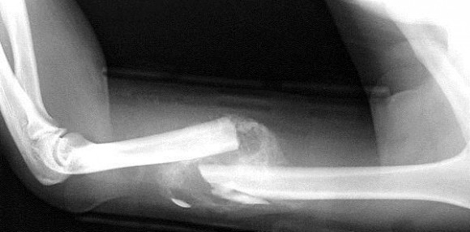

„Knochbrüche heilen einer Tierstudie nach schlechter, wenn der Organismus unter Dauerstress steht.“

„Bricht sich jemand das Bein, treten kurz danach an der Bruchstelle lokale Immunreaktionen auf. Der Körper sondiert sozusagen die Lage und beseitigt schadhaftes Gewebe. Mit der Zeit überwachsen Knochenzellen den bruchbedingten Spalt und der Bruch heilt ab“, erinnert Professor Anita Ignatius, eine der Autoren.

Bei langanhaltendem Stress kommt es jedoch zu Störungen dieser akuten immunologischen Prozesse und zu einem Überschießen der Entzündungsreaktion. So entwickeln sich einerseits im Knochenmark vermehrt Immunzellen wie Neutrophile Granulozyten, die an der Bruchstelle in die dort entstandenen Hämatome einwandern.

Andererseits ist die Umwandlung von Knorpel zu Knochen und damit die Knochenneubildung gestört, wie sich in der Ulmer Studie zeigte. Die Biegesteifigkeit der Knochen nimmt messbar ab, und das neu gebildete Knochengewebe an der Bruchstelle wird nicht mehr so hart.